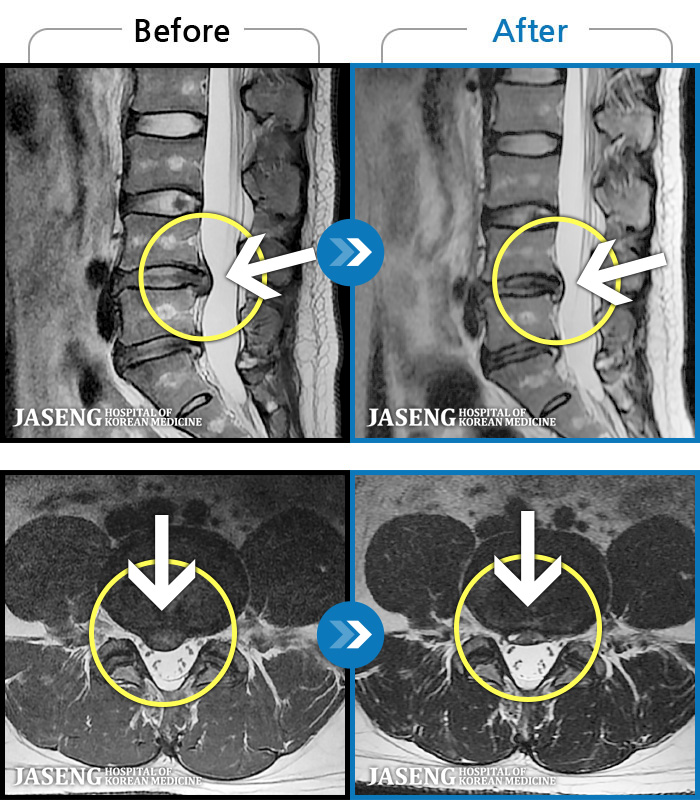

허리 골반 통증이 있고 다리가 저리고 아파 걷기가 힘들다.

2025.02.10 ~ 2025.09.13